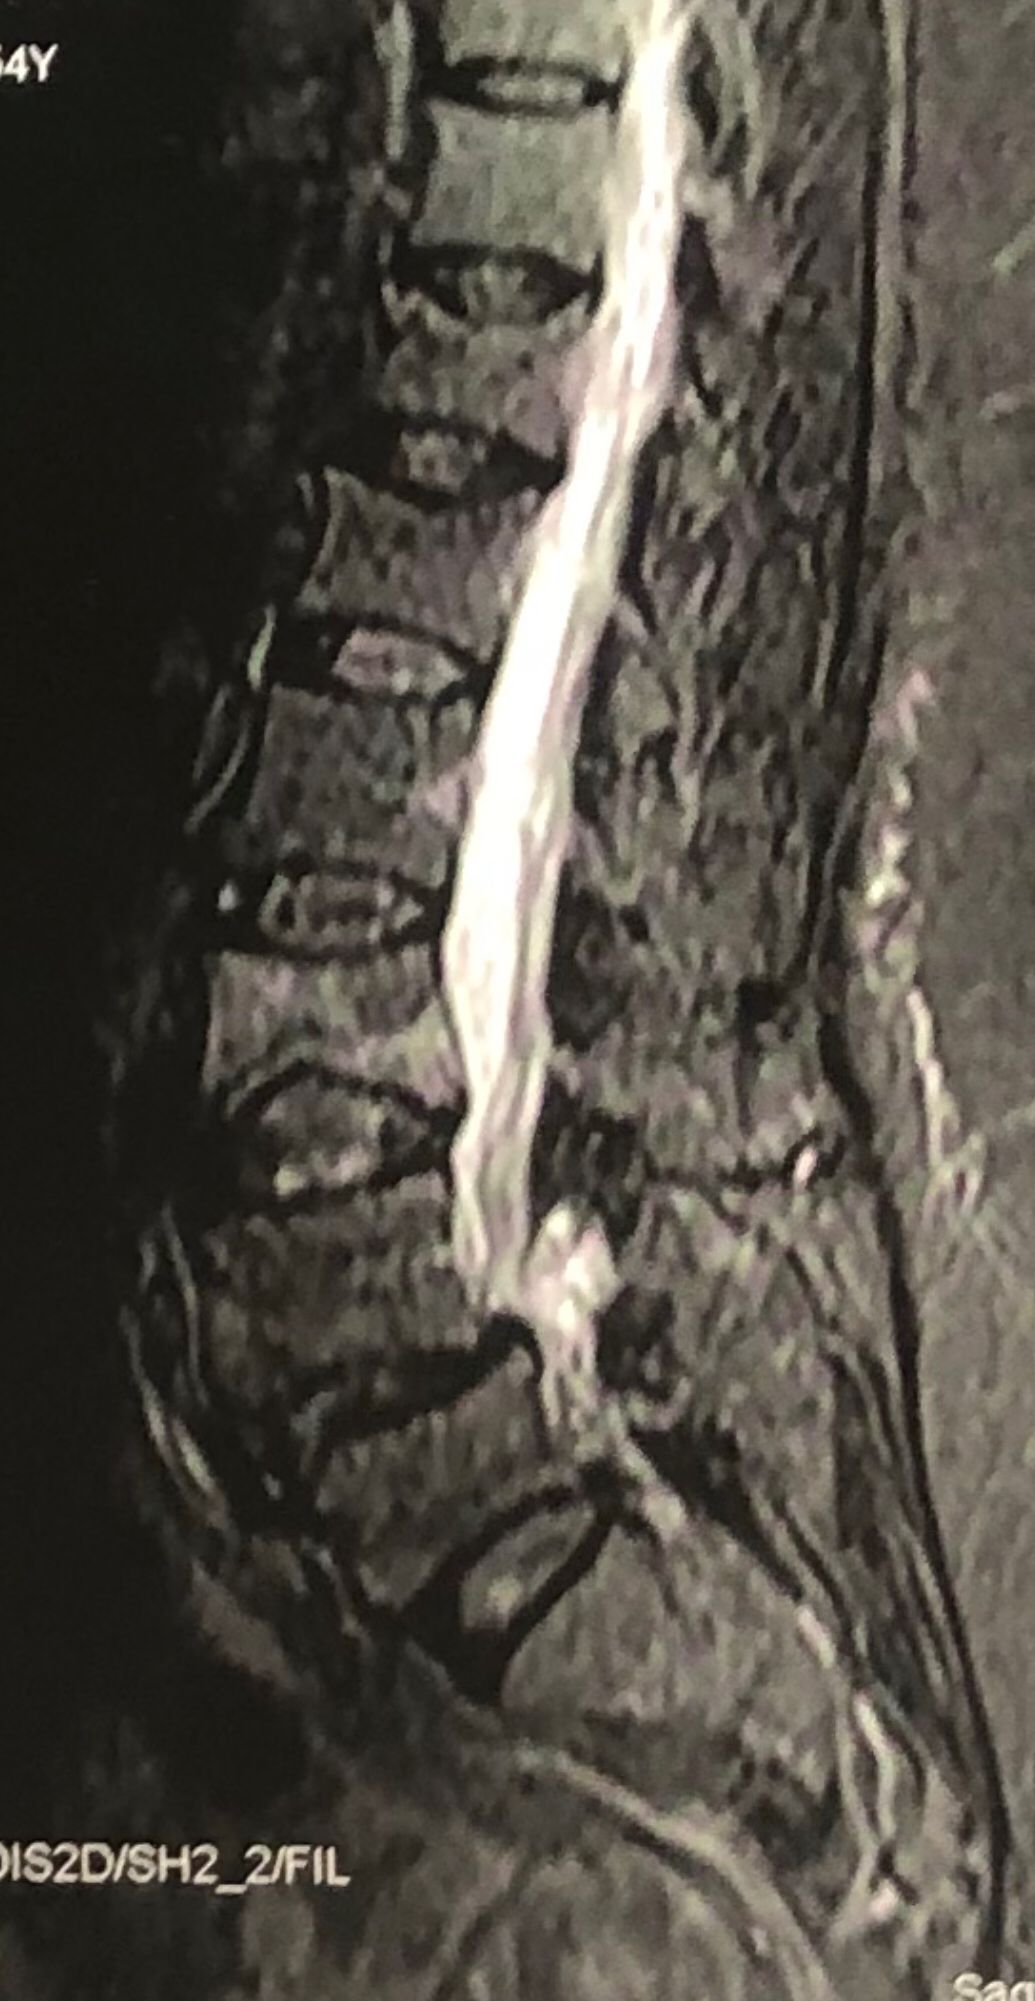

46 years old female patient presented to my clinic yesterday june 1/2025 with LBP and radicular L leg pain for several months which hasn’t responded to physio 2 neurosurgeons have visited her and didn’t suggest any surgery Neurological exam was unremarkable please see her mri/ emg/ncv and her huge tarlov cyst and possible L IVF L4-5 hyperbulge I ordered sacrum mri and ct scan and new emg/ncv and asked her with her sacral Ct scan and MRI first sees another two famous neurosurgeons and see if that large cyst is the reason for her pain if not i can work on her L4-S1 area Do you think her radicular pain can originate from her large cyst in sacrum? Do you consider surgery and removing her sacral cyst?